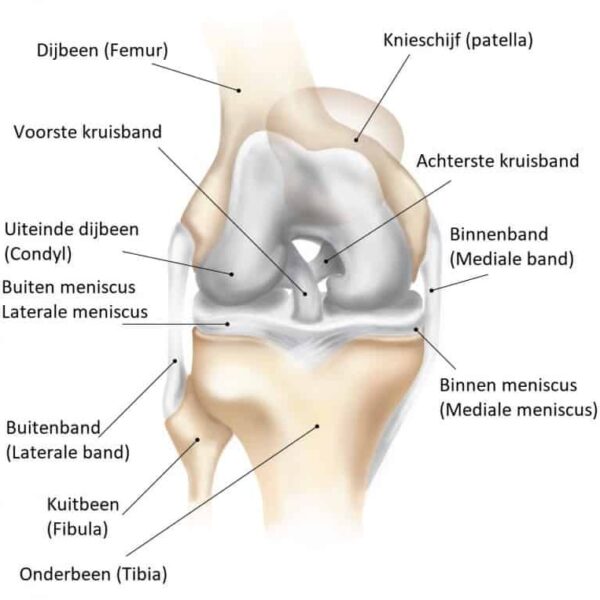

Anatomie en functie

De voorste kruisband, één van de belangrijkste band, loopt centraal in de knie. De functie van de VKB is het stabiliseren van de knie in voor-achterwaartse richting. De VKB bestaat uit twee bundels die in feite als één structuur functioneren, is ongeveer 25 tot 40 mm lang en heeft de diameter van een pink. De VKB heeft zenuwuiteinden die de hersenen informeren over de stand en de bewegingen van de knie.